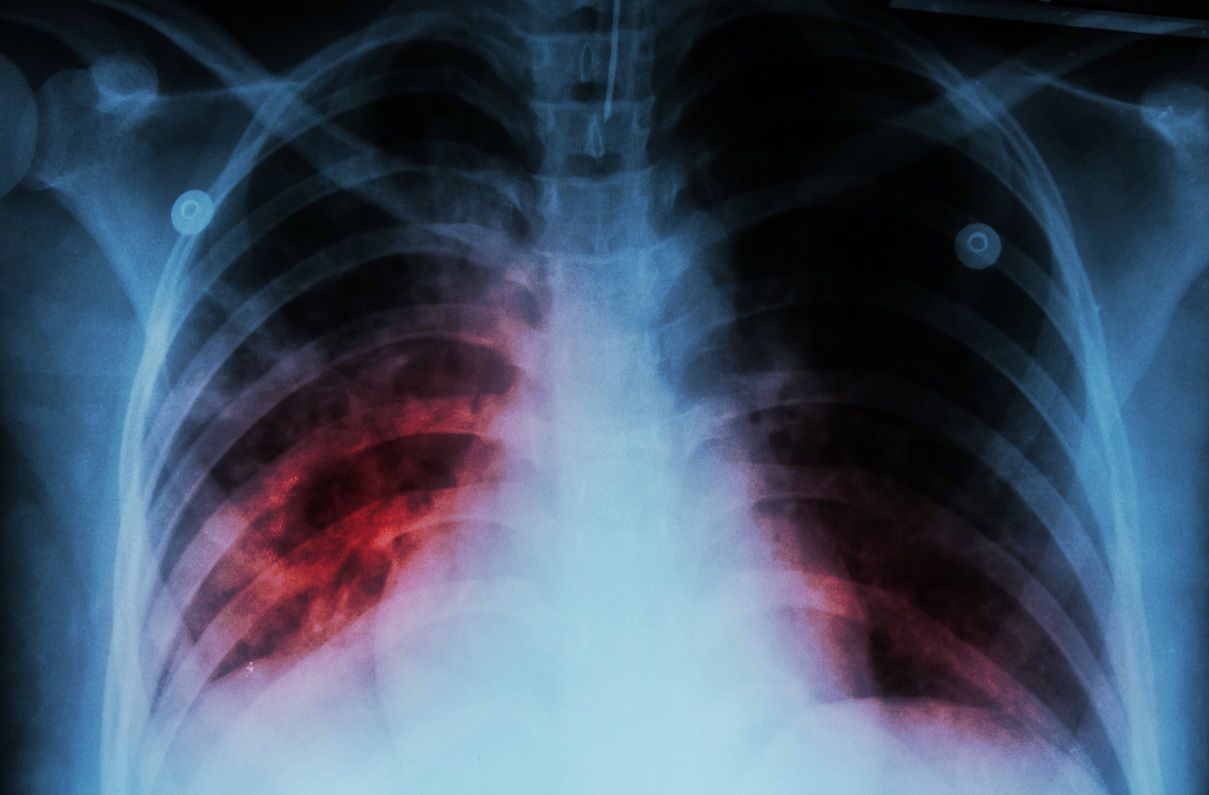

Zdjęcia pokazujące jak wyglądają płuca u pacjentów zaatakowanych przez koronawiurusa dają najlepsze wyobrażenie tego, do jakich spustoszeń może doprowadzić wirus.

To zdjęcie wykonane przez lekarzy z Akademii Medycznej w Chengdu u jednej z pacjentek zakażonych koronawirusem. Tomografia komputerowa klatki piersiowej wykazała zmętnienie w lewym górnym płacie płuca.